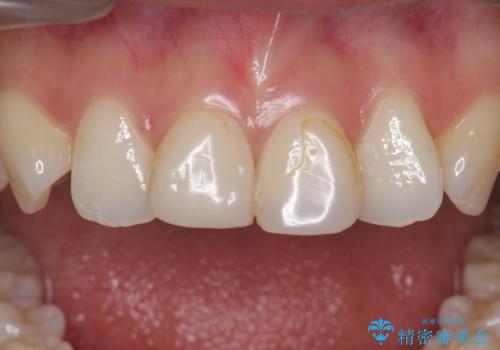

- 前歯の審美性改善と、軽度のがたつきを主訴に来院された患者様です。

マウスピース矯正を行った後、かぶせ物で審美性を改善していきます。

前歯には審美性も適合も良いクラウンを装着。

歯ぐきの状態も非常に良いです。